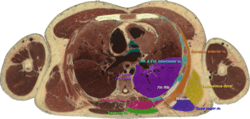

Cross section #1428 of the Visible Human Male showing the structures of the triangle of auscultation, created in the VH Dissector | |